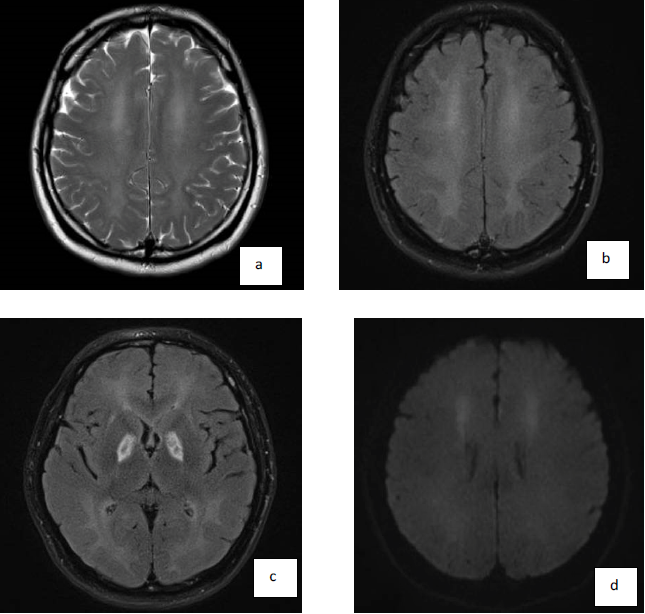

About 2 weeks later (around 3 weeks from the incidence), he was noticed to be less communicative and having difficulties in mobilization and performing activities of daily living. He was then transferred back for further evaluation. He was noticed to be withdrawn and not communicative. He had magnetic gait (hardly walked with freezing), limbs and truncal rigidity. Repeat MRI brain was done (Figure 3A, Figure 3B, Figure 3C and Figure 3D). He was treated with madopar and fluoxetine. He subsequently underwent rehabilitation.

Globus pallidus is the most commonly involved site in CO poisoning [1]. The predilection for the globus pallidus is unclear. However, it is probably related to CO binding to iron-rich globus pallidus or hypotensive effects of CO toxicity in the watershed arterial territory. Diffuse cerebral white matter demyelination (Figure 3A and Figure 3B) like what was observed in our case is believed to be responsible for interval form of CO poisoning. Restricted diffusion in both superior frontal subcortical white matter (Figure 3D) have shown the development of delayed cytotoxic edema, possibly due to delayed cell death and demyelination.

Figure 3: MRI brain done at day 31. A,B) Interval progression of extensive white matter changes with near confluent T2 weighted and FLAIR hyperintensity in both cerebral hemispheric white matter and near total loss of grey-white matter differentiation, in keeping with delayed demyelination; C) Interval decrease in swelling with residual cystic encephalomalacia in both globus pallidus; D) Interval areas of restricted diffusion in both superior frontal subcortical white matter/anterior corona radiata indicating ongoing neuronal white matter injury.